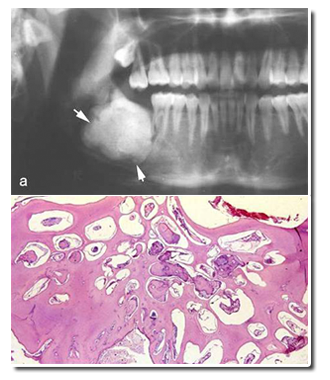

◇ 混合性牙瘤:儿童和青年上下颌骨均可发生,下颌前磨牙区和磨牙区多见。境界清楚的放射透光区,放射阻射性结节状钙化物。牙体组织成分排列紊乱相互混杂,发育期混合性牙瘤与成釉细胞纤维牙本质瘤和成釉细胞纤维牙瘤不易区别。生长有自限性。

◇ 组合性牙瘤:患者年龄较小,上颌切牙-尖牙区。形态和数目不一的牙样物堆积在一起。许多牙样结构组成,牙釉质、牙本质、牙骨质和牙髓排列,如同正常牙,预后良好。